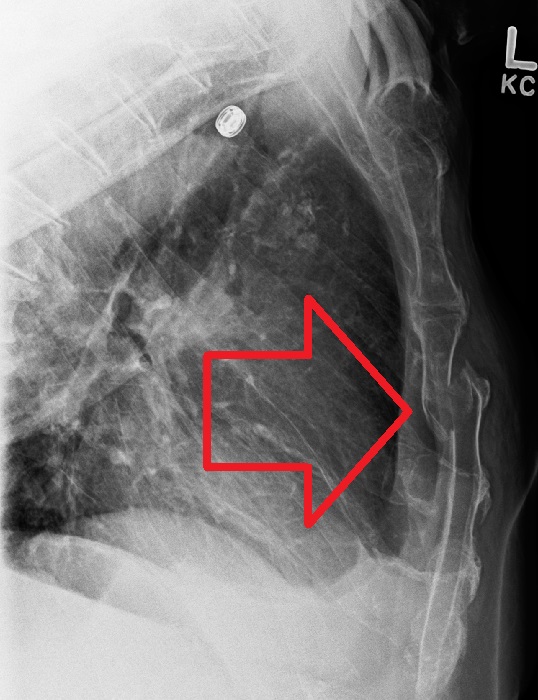

Взгляд рентгенолога: травмы грудной клетки.

Мультиспиральная КТ в диагностике тупой торакальной и абдоминальной травмы